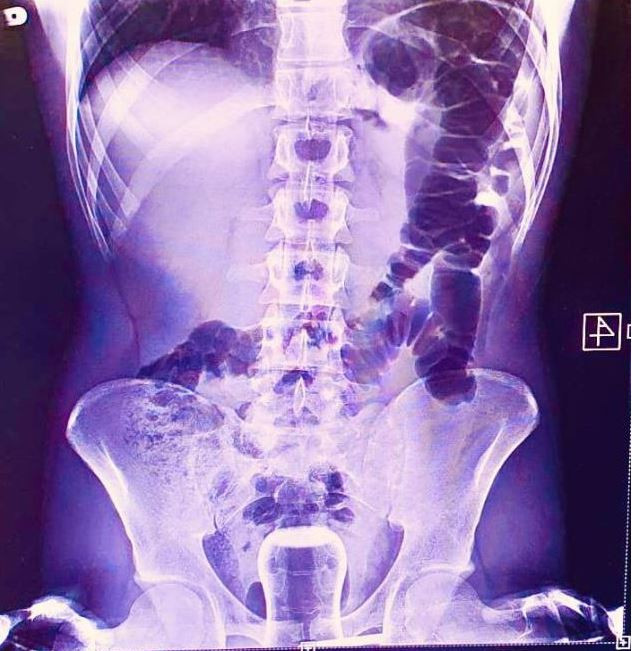

Doktorların görüp yok artık bu nasıl mümkün olur dedikleri röntgen filmleri..

Doktorluğun zor bir meslek olduğu malum. Üstelik bu mesleğin icra ederken bazı zamanlar öyle vakalar ortaya çıkmış ki, doktorlar bile anlamlandırmakta zorluk çekmişler.